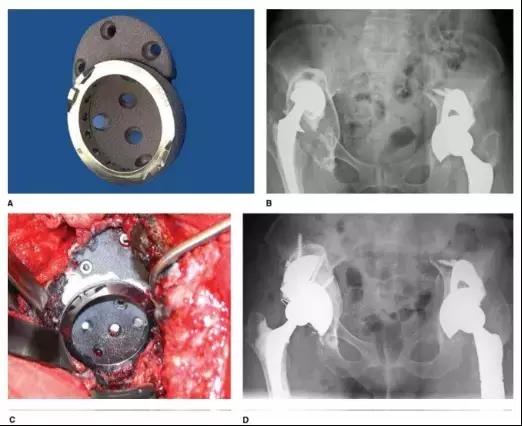

大杯(Jumbo)指臼杯直径在女性大于 62 mm、男性大于 66 mm 或翻修臼杯直径比初次髋臼大于 10 mm(图 1)。大杯是在不提供骨量重建的前提下将臼杯尽量放到足量宿主骨的一种既简便又有效的手段。目前大杯已成为主流选择,其中带钽金属骨小梁涂层的大杯即使只有 30% 的接触面积也能获得足够的生物骨长入。

图 1(A)APR 髋臼假体(B)InterOp 髋臼假体

近年来钽金属块问世,其有更好的骨长入面积和抗剪切界面强度,而且较高的摩擦系数可以保证初始稳定,这些对臼杯获得远期生物固定非常关键。联合结构性植骨或金属骨小梁垫块可解决 Paprosky III A 及大部分 III B 型骨缺损,中远期随访结果良好(图 3、4)。

图 3 (A)多孔钽金属垫块置于非骨水泥髋臼假体上方 (B)术前 X 线提示右 IIIA 型髋臼骨缺损 (C)术中非骨水泥髋臼假体联合多孔金属加强块 (D)右髋翻修术后 X 线